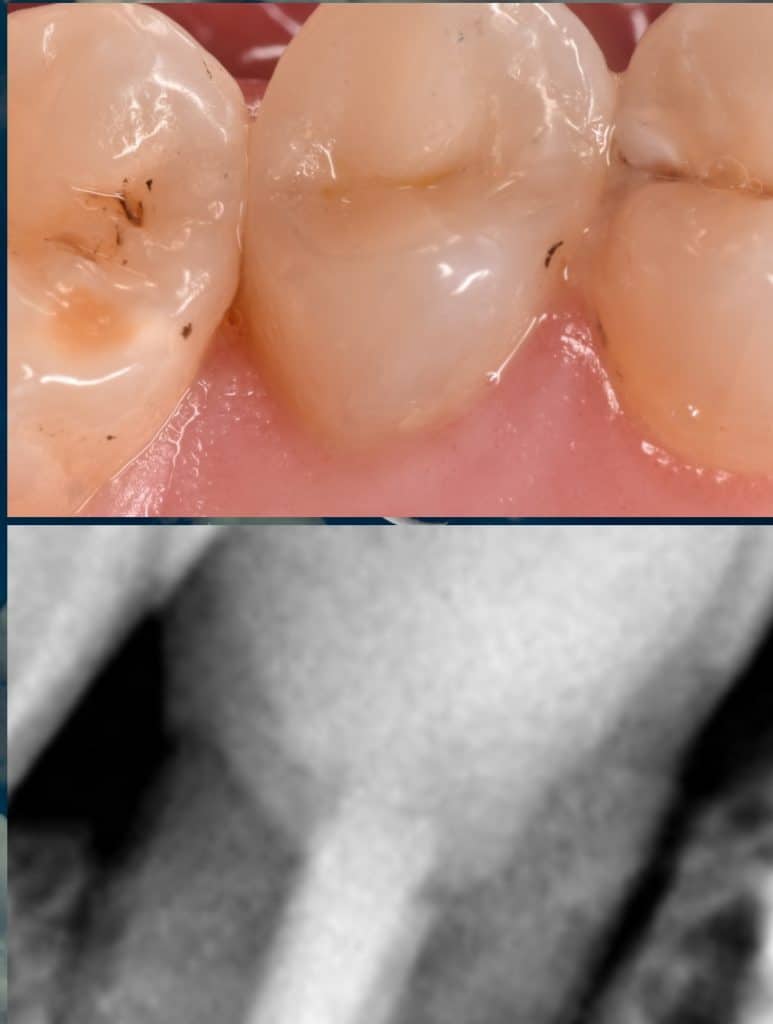

14 months follow-up